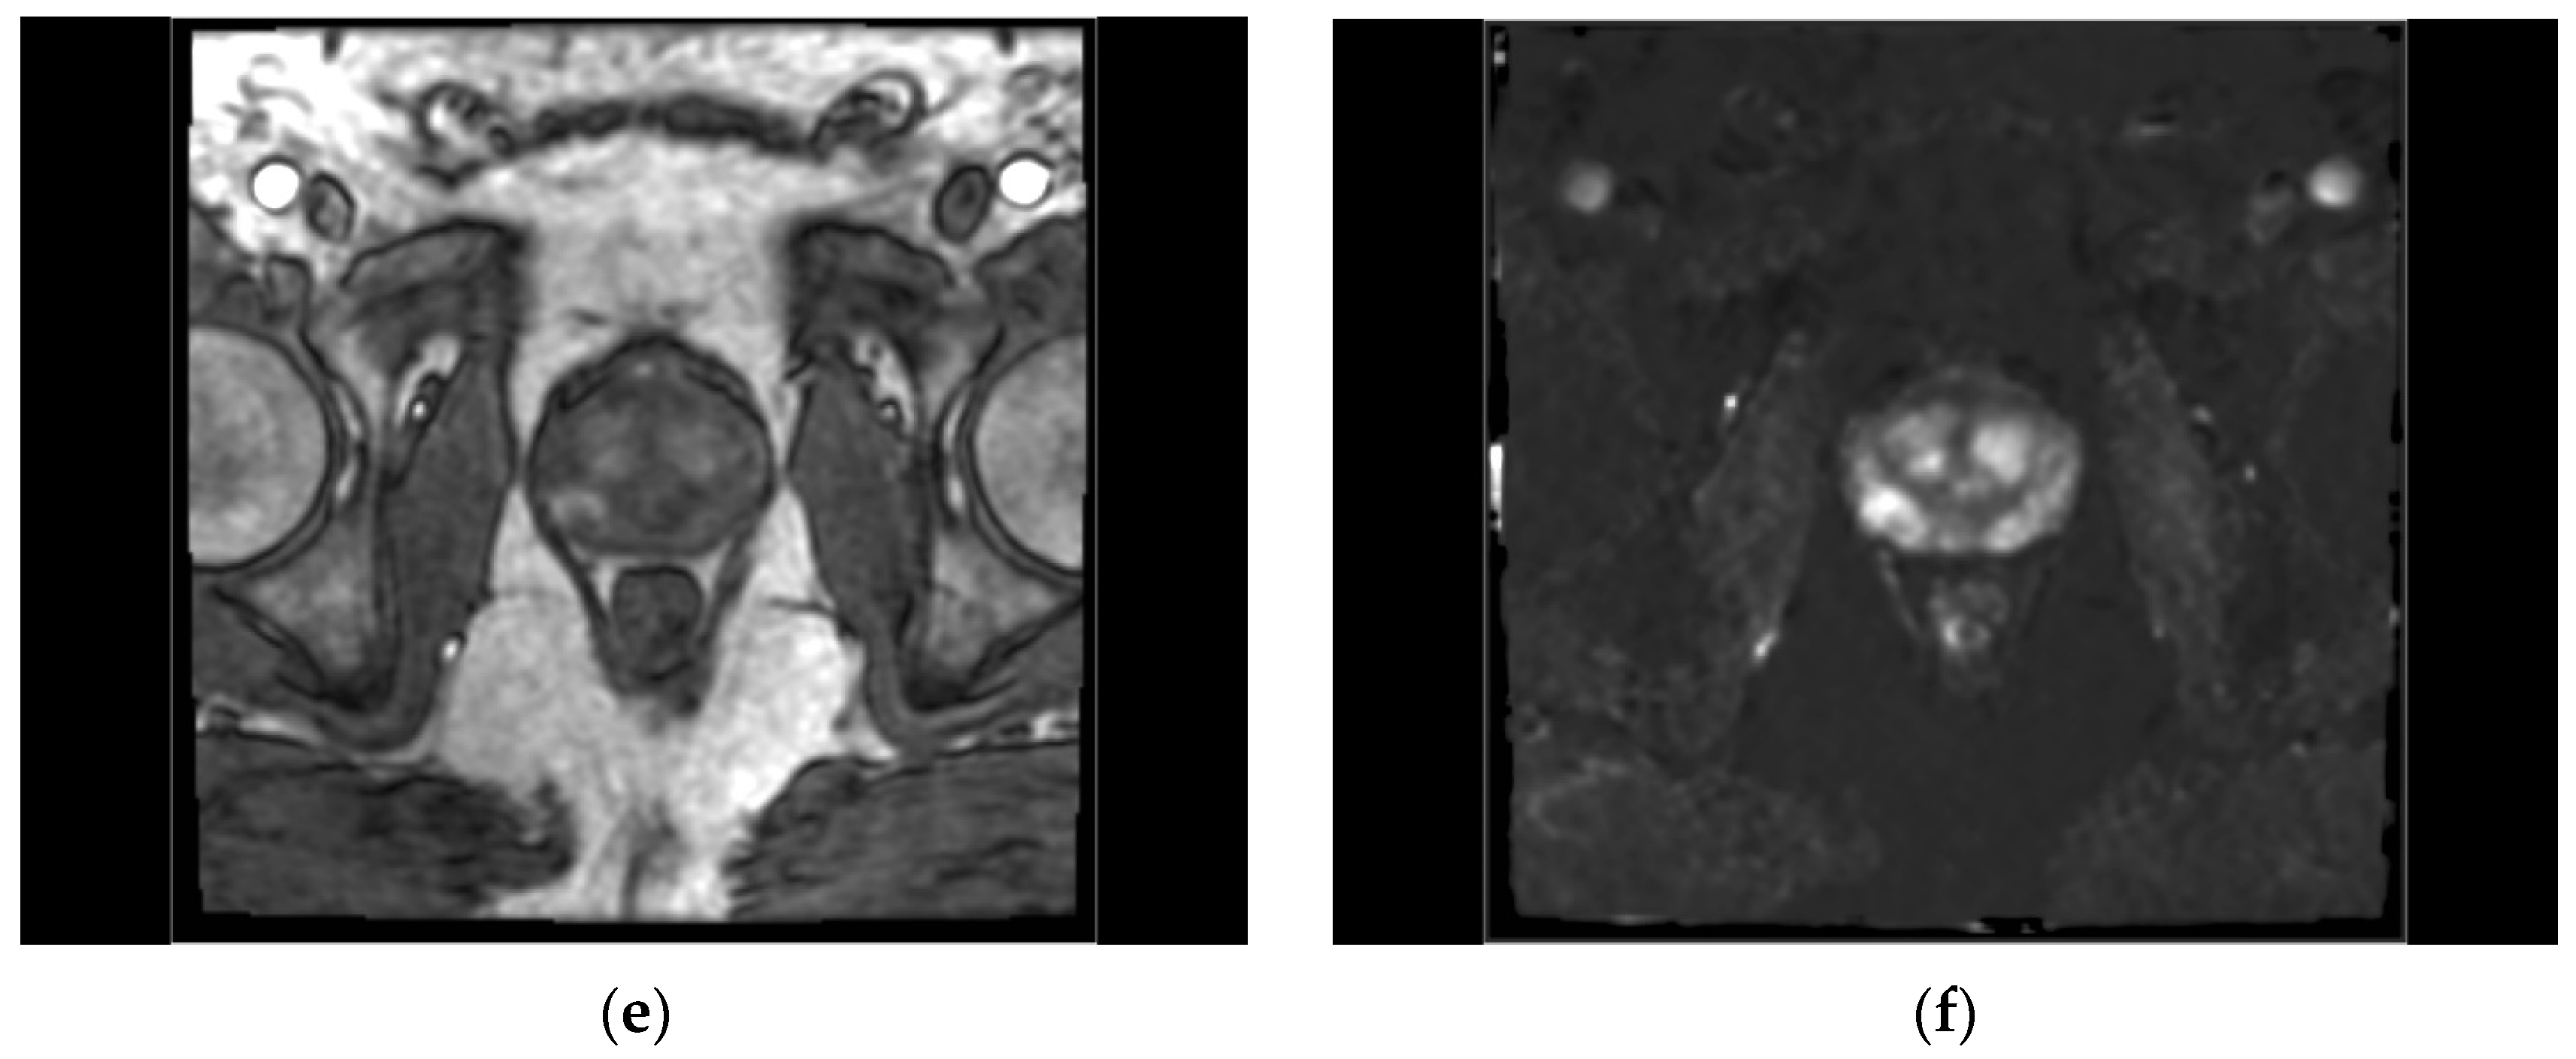

2.4. Region of Interest Definition

2.5. Radiological and Pathological Evaluation